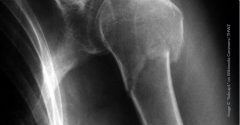

Eine etwa 70-jährige Frau stellt sich mit schmerzverzerrtem Gesicht in der Notaufnahme vor. Mit der rechten Hand hält sie ihren angewinkelten linken Arm eng am Brustkorb. Sie sei gefallen, habe sich aber mit gestreckten Armen abfangen können – dabei habe sie ein Knacken nahe der linken Schulter vernommen. Die Röntgenaufnahme zeigt eine Humeruskopffraktur. Operieren oder nicht?

Die Humeruskopffraktur macht etwa 6 % aller Knochenbrüche aus. Während Brüche des Schafts oder des distalen Oberarmknochens eher bei jüngeren Menschen auftreten, ist die Humeruskopffraktur – wie in unserem klinischen Beispiel – ein typischer Knochenbruch des Alters. Sie betrifft Frauen etwa doppelt so häufig wie Männer und geht oft mit Osteoporose einher. Mehr als zwei Drittel der Betroffenen sind älter als 60 Jahre 1, was die Humeruskopffraktur zum dritthäufigsten Knochenbruch in diesem Alterssegment macht 2.